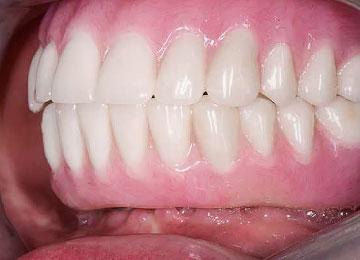

Имплантация All on 4: фото До и После

- Искусственные зубы невозможно отличить от натуральных, высокие эстетические показатели;